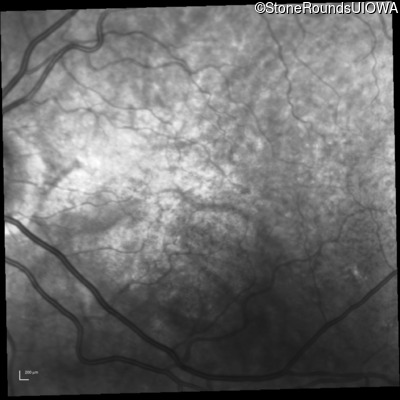

Fluorescein Angiography - Left - 20/30 -2 sc

Exemplar